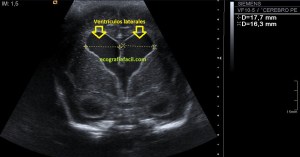

Con la eco pasa igual…cuando queremos estudiar, por ejemplo, el recto anterior del muslo en axial,perfecto…pero en longitudinal, como la imagen 2, se complica porque desde la rótula a la inserción en la cadera, tenemos mucho recorrido. En este caso hacemos lo mismo que cuando hacemos la foto del atardecer…nos ponemos en un extremo, activamos la funciona, recorremos suave y continuamente por la anatomía que queremos fotografiar y ya está…mira la pantalla y no el movimiento de tu mano,como si hicieses la foto, ves la pantalla,pero no como mueves el teléfono.